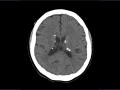

Esclerose tuberosa

Mai de 2016.

12.871

tumor subependimário

Ressonância magnétic...